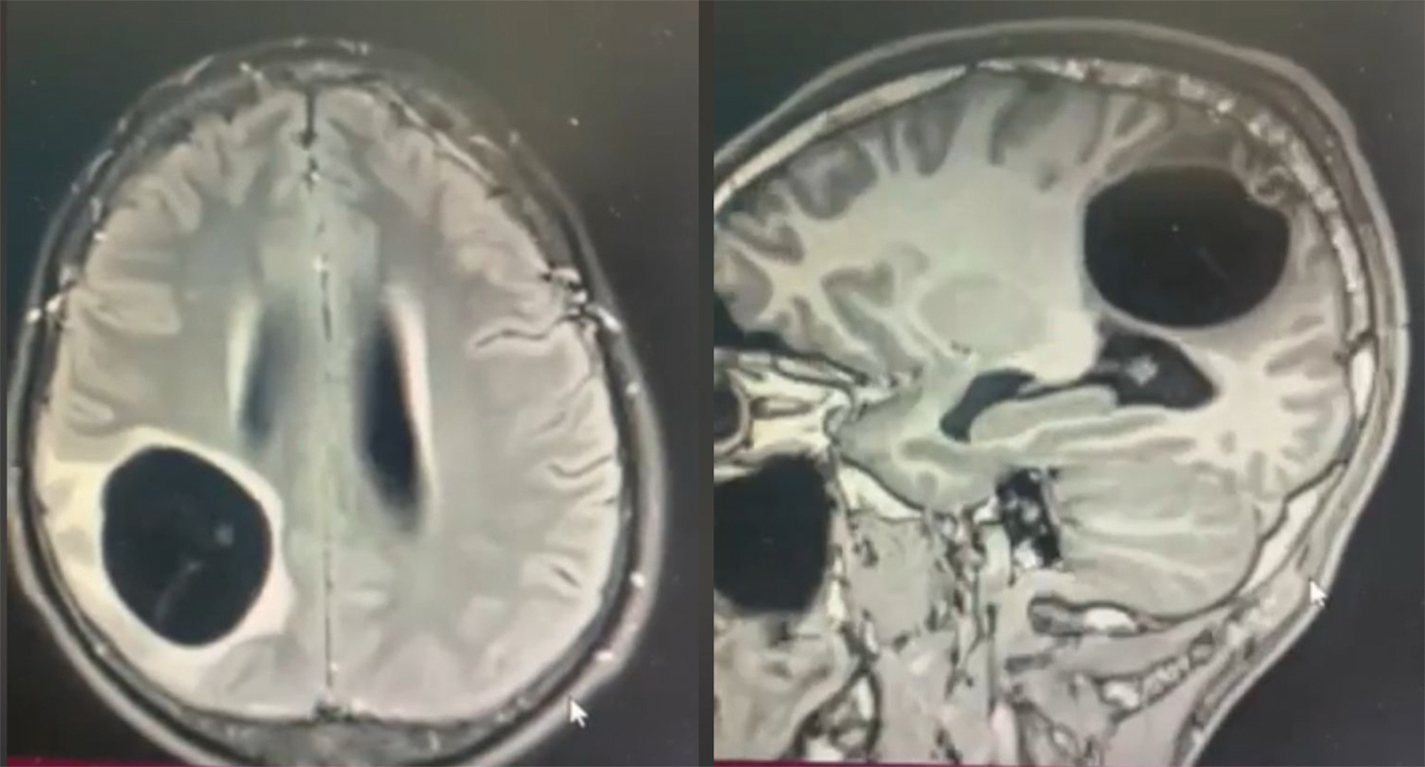

The CT-scan cerebral revealed a large cyst, parietal-right lobe, spontaneously hypodense, without contrast uptake, oval shape and regular contours (Fig. 1). The cyst had an important mass effect on the adjacent cerebral parenchyma, especially in the right parietal lobe.

Fig. 1. CT scan showing a hydatic cerebral cyst located at the right parietal level, with microcalcification in the posterior wall of the cyst (bright blue arrow).

Imaging is essential in the positive diagnosis and pre-therapeutic assessment of cerebral hydatic cyst. X-ray of the skull was not performed in our case; but authors report a voluminous calcification of the cranial vault visualized on radiography corresponding to a calcified cerebral hydatid cyst [12]. The current diagnostic tools are CT and MRI brain. The CT scan cerebral is the key examination, making a positive diagnosis of a hydatid brain cyst in almost all cases. It typically shows, as in our observation, a cystic mass, round or oval with clear contours, thin-walled, of density equivalent to that of the cerebrospinal fluid (CSF) associated with an important mass effect [1], [8], [9]. The cerebral hydatid cyst does not usually increase after injection and is not accompanied by perilesional edema [1], [10], [13]. The almost constant absence of peripheral enhancement by contrast product is explained by the thinness of the pericyst in the brain and by the adhesion of the hydatid membrane to the brain [9]. However, cases of hydatid cerebral cyst with contrast uptake and peripheral edema have been reported in the literature [9].

The hydatid cyst is often a single, intra-parenchymatous, supratentacular lesion, well limited, often spherical, with a density identical to that of cerebrospinal fluid, its wall is thin and is not enhanced by contrast, There is no peri-lesion edema [16]. Sub-tensor locations, especially cerebellar ones, are rare.

In our case, the lesion was unique, of supra-tensor seat in posterior parietal right lobe, without contrast, spherical and we note a presence of calcification at the level of the cystic wall. According to Choukri [17] and Benzagmont et al. [18], calcifications within the cyst during its involution usually mark death and inactivity of the parasite.